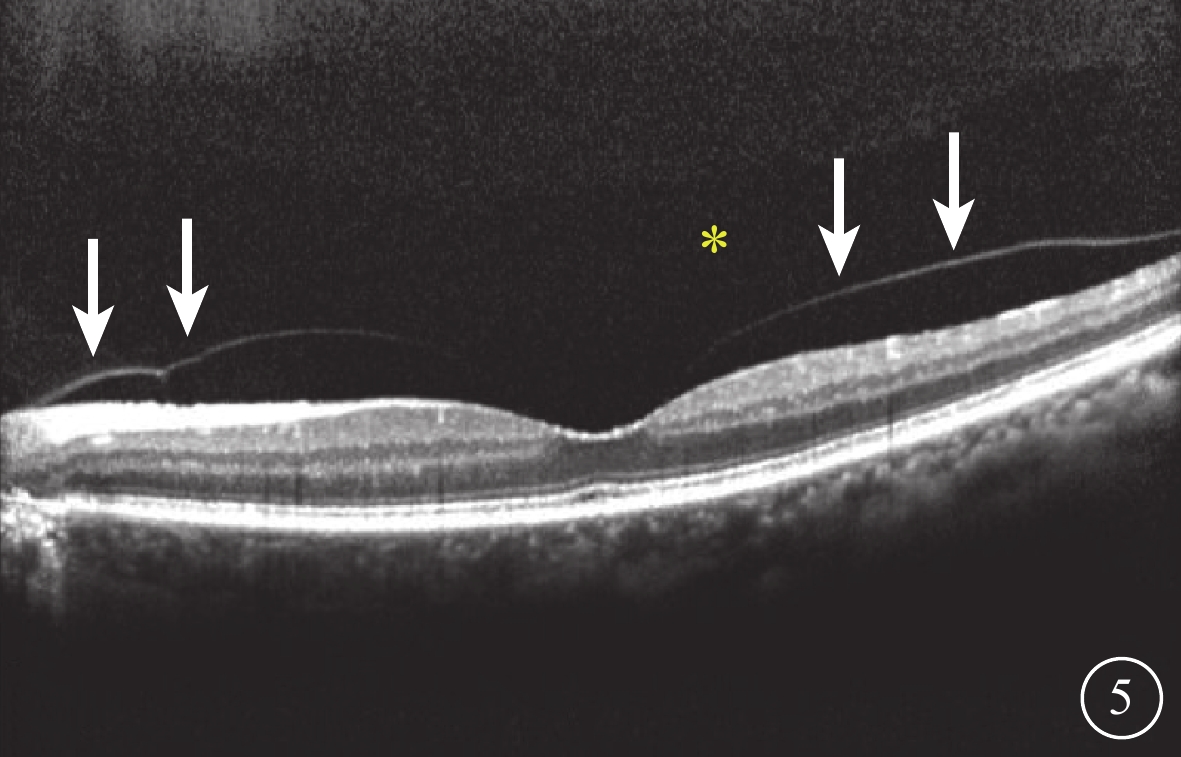

圖5

受檢眼SD-OCT像。PPVP(黃星)伴不完全性PVD(白箭)

圖5

受檢眼SD-OCT像。PPVP(黃星)伴不完全性PVD(白箭)

SD-OCT檢查,所有受檢眼常規檢查均未觀察到PPVP。后極部玻璃體掃描模式所采集的圖像可見PPVP結構清晰,表現為黃斑區前弱反射船形腔隙,前界為玻璃體膠原,后界為玻璃體皮質(圖2)。所有受檢眼PPVP鼻側存在一弱反射的無凝膠區域(Martegiani區),兩者之間有一隔膜將其分開。其中,單線掃描可見PPVP與Martegiani區之間存在連接通道(圖2)68只眼(66.0%);多線掃描可見所有受檢眼PPVP與Martegiani區存在連接通道,通道在某些層面出現(圖3)。PPVP前可見一個或多個黃斑上囊(圖2)16只眼(15.5%),其中黃斑上囊與PPVP之間相互連通(圖4)5只眼。PPVP伴玻璃體后脫離(PVD)(圖5)9只眼。采用FDI掃描模式進行檢查的21只眼,視網膜、脈絡膜成像清晰度較好,但玻璃體成像清晰度較差(圖4)。60只眼的PPVP平均最大水平距離為(6 895.7± 872.8)μm,平均垂直距離為(524.1±173.9)μm。

圖5

受檢眼SD-OCT像。PPVP(黃星)伴不完全性PVD(白箭)

圖5

受檢眼SD-OCT像。PPVP(黃星)伴不完全性PVD(白箭)